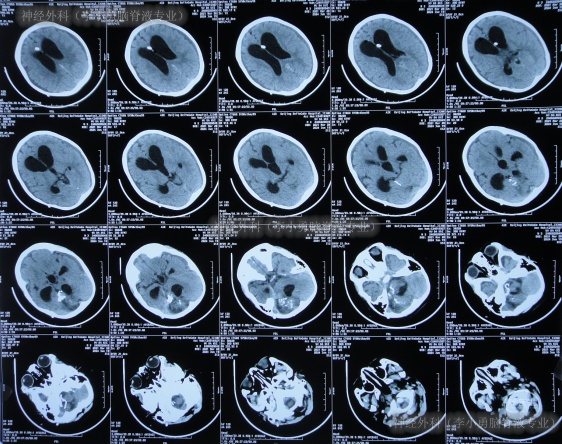

术后症状有短暂好转后但又出现了双眼凝视,精神状态差,术后5天的时间内2次查头颅CT示脑室再次明显扩大(图-1),持续Ommaya囊外接引流瓶引流脑脊液。

图-1:2次查头颅CT该院继续治疗40天,期间6次查头颅CT(图-2)均示脑室扩张不断地加重。

图-2:6次查头颅CT